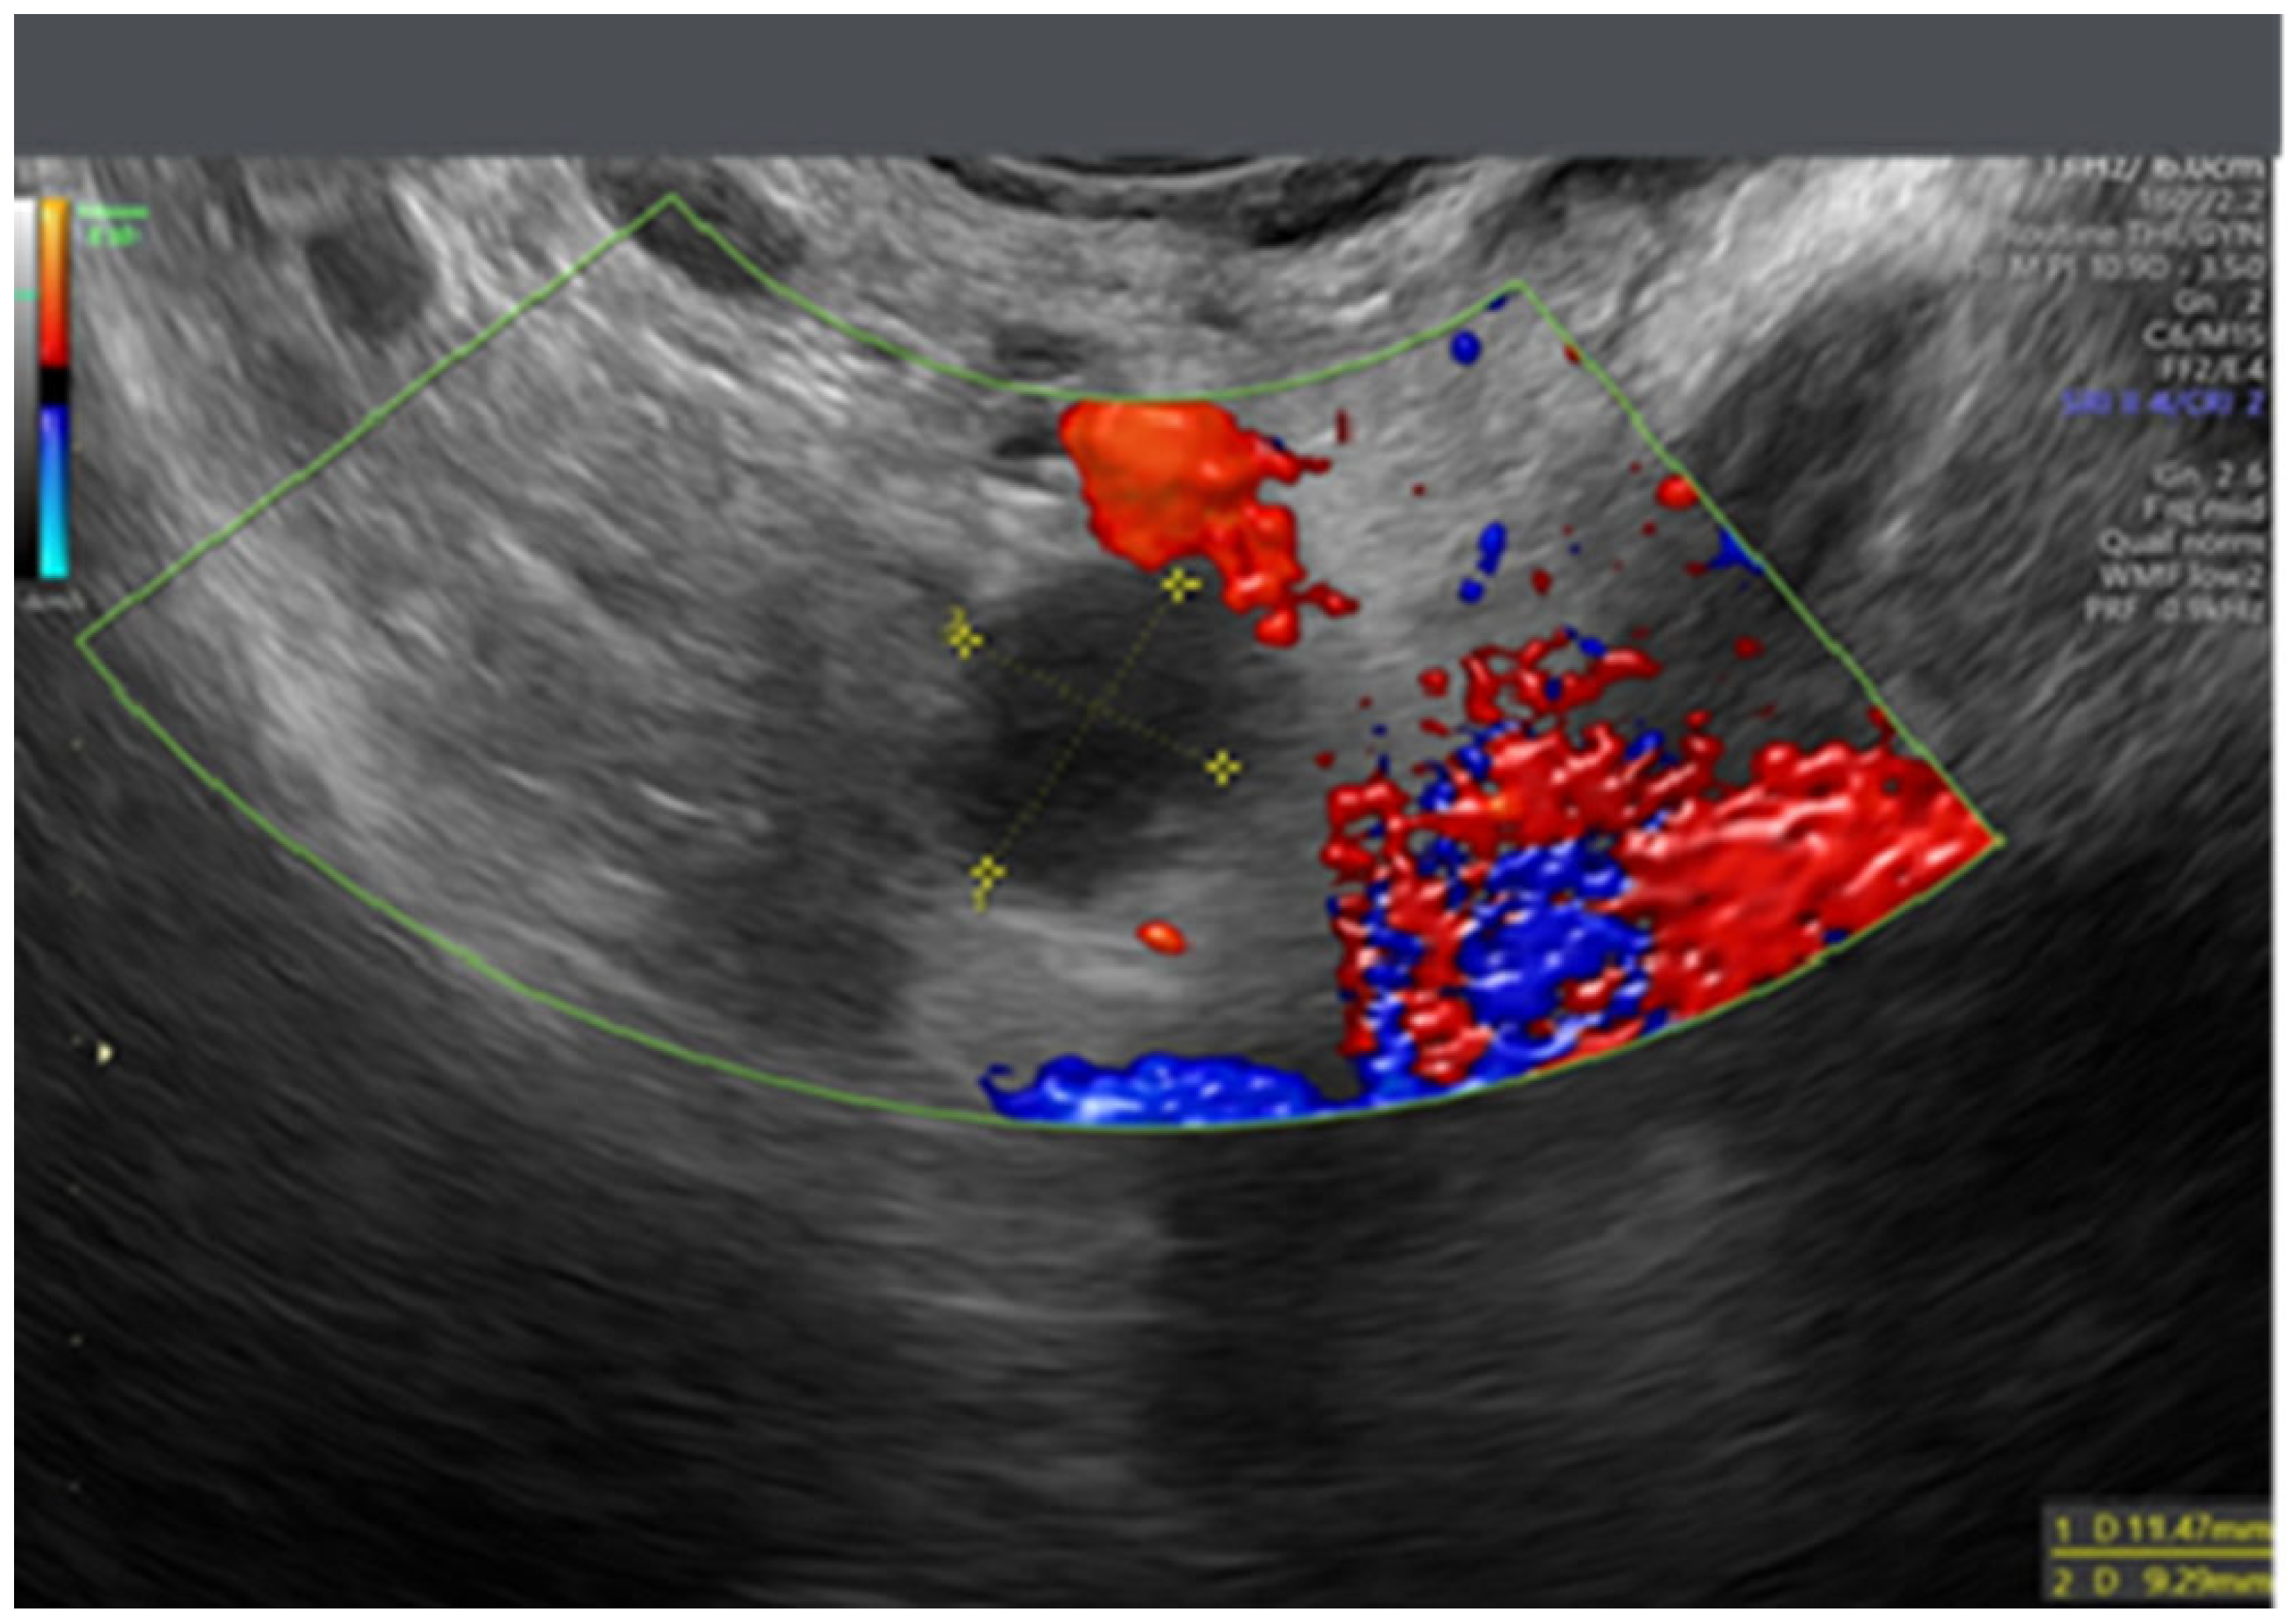

- Testa, A.C.; Ludovisi, M.; Savelli, L.; Fruscella, E.; Ghi, T.; Fagotti, A.; Scambia, G.; Ferrandina, G. Ultrasound and color power Doppler in the detection of metastatic omentum: A prospective study. Ultrasound Obstet. Gynecol. 2005, 27, 65–70. [Google Scholar] [CrossRef]

- Testa, A.C.; Ludovisi, M.; Mascilini, F.; Di Legge, A.; Malaggese, M.; Fagotti, A.; Fanfani, F.; Salerno, M.G.; Ercoli, A.; Scambia, G.; et al. Ultrasound evaluation of intra-abdominal sites of disease to predict likelihood of suboptimal cytoreduction in advanced ovarian cancer: A prospective study. Ultrasound Obstet. Gynecol. 2012, 39, 99–105. [Google Scholar] [CrossRef]

- Fischerova, D.; Zikan, M.; Semeradova, I.; Slama, J.; Kocian, R.; Dundr, P.; Nemejcova, K.; Burgetova, A.; Dusek, L.; Cibula, D. Ultrasound in preoperative assessment of pelvic and abdominal spread in patients with ovarian cancer: A prospective study. Ultrasound Obstet. Gynecol. 2017, 49, 263–274. [Google Scholar] [CrossRef]